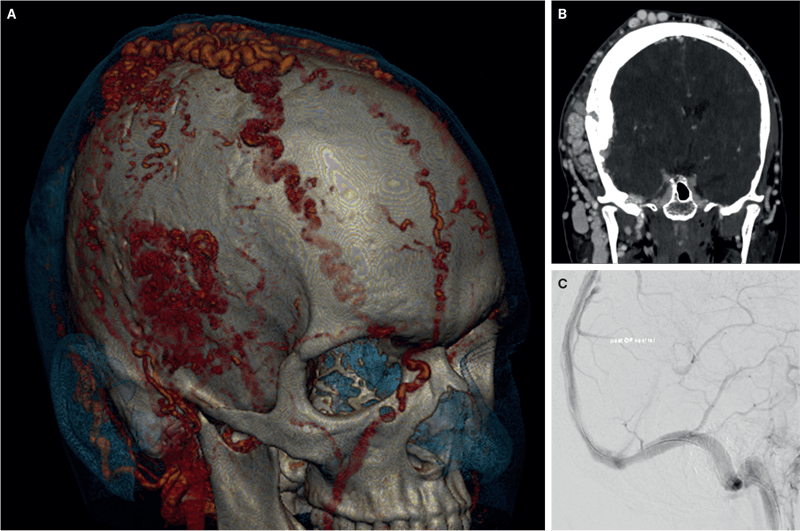

På grund af blød udfyldning på skalpen blev en asymptomatisk, 22-årig mand i august 2015 henvist til CT af cerebrum, der afslørede en monstrøs high-flow ekstrakraniel arteriovenøs malformation (eAVM) (A og B). Qua supplerende digital subtraktionsangiografi, der demonstrerede diskret højresidig intrakraniel involvering og anastomoser med a. carotis externa-grene bilateralt samt a. vertebralis og a. ophthalmica dxt, var der formodning om steal-fænomen (SF). Dertil var der fortykkede kranieknogler på højre side (B) som tegn på kronicitet med karakteristisk ukendt ætiologi [1, 2].

I de følgende år debuterede patienten med forbigående kvalme, hovedpine og flimren for højre øje. Hovedpinen persisterede, og på grund af højresidig konstant tinnitus blev han i juni 2023 henvist til CT-angiografi. Nytilkommen svær stenose af dominant (højre) sinus transversus (dST) blev afsløret. I oktober 2023 gennemførtes stentning af dST for at mindske risikoen for hæmoragisk infarkt på grund af SF.

I april 2024 viste kontrolskanningen pænt flow gennem stenten (C), og antitrombotika blev seponeret. Tinnitus var uændret. En eAVM-behandling inkluderede embolisering og resektion, men der eksisterer ikke behandlingsstandardisering [3, 4]. Som følge af karmalformationens omfang vurderedes tilstanden inkurabel, og patienten blev afsluttet på trods af diskret vækst af eAVM og vedblivende tinnitus.